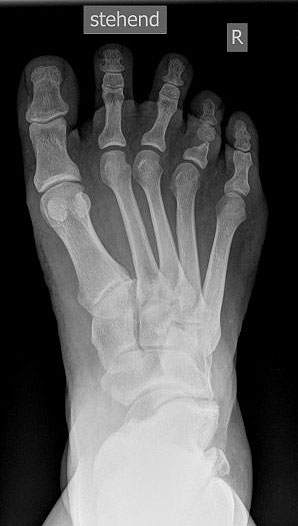

• Fuß belastet dp und seitlich (Abb. 14 und 15)

Typische Merkmale der Standard-dp-Röntgenaufnahme des Fußes im Stand

• Talus und Calcaneus verlaufen fast parallel

• Os naviculare ist gegenüber dem Talus nach medial gedrängt

• Metatarsalia überlappen sich basisnah

• Metatarsale I erscheint verkürzt

• Metatarsus adductus